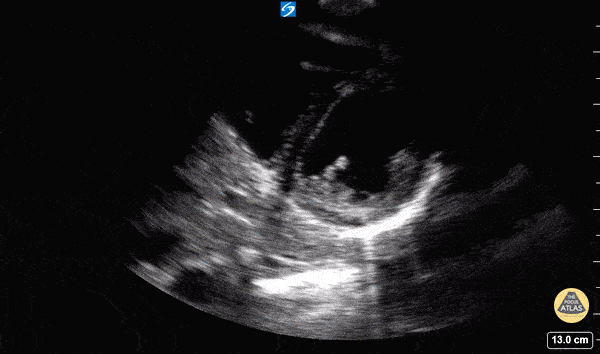

Parasternal Long Axis

• ANATOMIC LANDMARK: left sternal border, 3-4th interspace

• Probe marker to the right shoulder

• SONOGRAPHIC LANDMARK: HEART

• Identify:

• LV, RV, LA, MV, AV

• Pericardium +/- Pericardial/pleural fluid